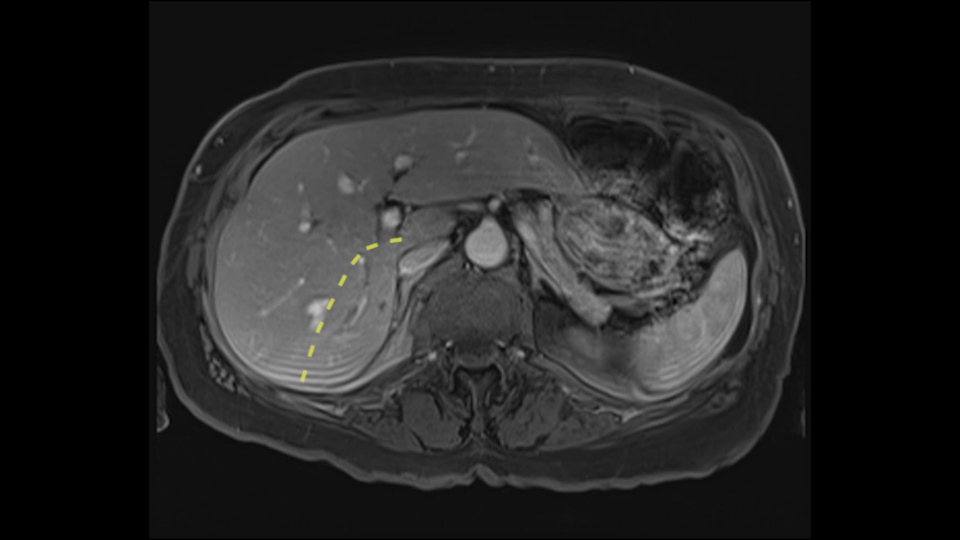

The third issue for this patient is that in Segment 7, I notice that there is intrahepatic ductal dilatation due to a small tumor causing obstruction. Now this tumor is not well-visualized on the most recent CT scan but I want to carefully evaluate the bile duct, where the obstruction is, so at the time of surgery I can be sure to remove the affected bile duct as well as the small tumor that is causing the ductal dilatation.

![[before chemo]](jpg/preop_aw_moment8.jpg)

So in light of the CT findings, the plan for this patient is a right hemihepatectomy that would encompass all the small tumors including the one in 4a-8, 5, 6-7; and the reason that I would do a full right hemihepatectomy is because of the intraductal dilatation in Segment 7 that makes me suspicious that there is a tumor that cannot be removed with simple wedge resections.

My name is Steven Gallinger, I’m a professor of surgery at the University of Toronto and an HPB surgeon at the University Health Network. I’ve been asked to comment on this case and discuss preoperative planning, potential slowing down moments. It’s an interesting 65-year old woman with right sided colon cancer and synchronous liver metastases: small metastases in the right lobe of the liver and she had the primary tumor resected and then underwent neoadjuvant chemotherapy for her small liver metastases in Segments 4, 5, 6 and 7. The distribution of the metastases is interesting. They are small lesions, but the interesting additional feature is isolated segmental dilatation of the Segment 7 bile duct which suggests an intrabiliary metastasis somewhere near the origin of the main Segment 7 duct. Because I can trace it close to the porta [hepatis], I would assume that it’s pretty close to the bifurcation of the main right sided bile ducts but I can’t actually see the actual tumor. It’s really just presumptive.

She underwent neo-adjuvant chemotherapy and then had a series of additional investigations and the one that I’m focusing on in more finer detail is an MRI with Primovist and I’ve had the benefit of looking at the report. The main issues are in Segments 5,6, and 7. Three small metastases that remain and the radiologist also comments on the lack of biliary dilatation which was present before; implying that the intrabiliary metastasis somewhere at the origin of the Segment 7 duct, has regressed or been adequately well treated with chemotherapy. That’s probably where the difficult decision making comes in the OR. So from an oncologic point of view, I would plan for a right hepatic lobectomy. The rationale would be that this would include the more peripheral Segment 5, 6, 7 metastases that are obvious but also would take care of the presumed Segment 7 intrabiliary metastasis that does not actually visualize on any of the scans but is assumed to be there with evidence of the duct dilatation which then resolved. One could argue whether we should preserve liver and ignore that duct dilatation that was there before but I think my own preference would be to resect the right lobe and that would certainly include any residual disease in that Segment 7 bile duct and moreover, coming back to do a completion right hepatic lobectomy would be difficult particularly around the porta where this metastasis is presumably still there and even if its quite small.

I am Professor Jacques Belghiti, hepatobiliary surgeon. I practiced at Beaujon Hospital at Paris Diderot University Paris 7. I will discuss the case of a 65-year old patient who has hepatic metastases from a colon cancer operated on one year before. Two particular points with this patient: She has had a cholecystectomy at the time of colectomy, and at the discovery of the lesions in which there were 3, all located in the right liver, we noted the existence of biliary dilatation. This biliary tract dilatation could have been a consequence of the cholecystectomy, or due to a particular form of metastasis with biliary infiltration; and my impression is that the second hypothesis should be supported for two reasons. The first reason is that on the initial CT scan, we had a feeling that the biliary tract dilatation was associated with a small tumor/lesion. The second reason is that the dilatation decreased after several courses of chemotherapy. I don’t know how many courses of chemotherapy she had, but in any case, there exists some lesions of the hepatic parenchyma, with steatosis that may have been a consequence of this chemotherapy. After several courses of chemotherapy, we see at least 2 lesions persisting in the posterior sector of the right liver and dilatation of the biliary tracts. There might be another lesion at the junction of Sg 5 and 8. So this patient should now be operated on since we are faced with lesions that persisted after chemotherapy.

It’s been a few years, I would have done a right hepatectomy. I think it is more sensible now, especially taking into account the current Japanese and Asian practices, to do a more limited operation. So my option will be a generous hepatectomy by traditional ways. I would not do laparoscopic, not because I don’t think it’s good but because I usually don’t do laparoscopy. By classical sense, a formal hepatectomy, a thorough evaluation of the liver manually, visually, and with intraoperative ultrasound to locate all the areas, notably any scarred tissue that could be left behind from previous metastases that shrunk under chemotherapy. In 90% of cases, even if the lesions are not visible on CT or MRI, they are detectable as a form of scarring that should be seen by ultrasound, and you have to find them after having evaluated on ultrasound or by palpation. If I don’t find any other lesions, I would revise for a posterior sectorectomy, taking out Sg 6 and 7 in a generous fashion to get the biliary involvement, and a local resection of the Sg5-8 lesion.